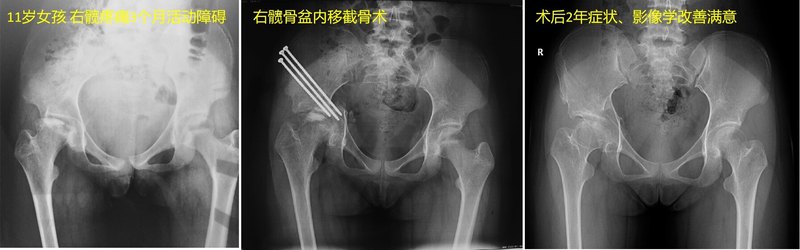

前面幾期科普我們知道了Perthes病是兒童期不明原因的股骨頭供血異常、缺血壞死。臨床上還會(huì)遇到另外一種情況,就是髖部創(chuàng)傷特別是股骨頸骨折后發(fā)生的股骨頭缺血壞死。兩者從發(fā)病機(jī)制、病程特點(diǎn)、影像學(xué)表現(xiàn)、修復(fù)能力、自然轉(zhuǎn)歸等方面均存在巨大差異,相應(yīng)的,治療選擇也不能簡(jiǎn)單套用Perthes病的治療理念與手段。兒童創(chuàng)傷后股骨頭壞死特殊在哪里??jī)和瘎?chuàng)傷后股骨頭壞死多發(fā)生于大齡兒童與青少年[1]。創(chuàng)傷后股骨頭壞死具有疾病進(jìn)展快、病理改變復(fù)雜以及不良預(yù)后風(fēng)險(xiǎn)較高等特點(diǎn)[2]。但是相對(duì)于成人股骨頭壞死,兒童創(chuàng)傷后股骨頭壞死仍具有一定的股骨頭修復(fù)與重塑能力。下圖所示均為青少年期髖部外傷后發(fā)生股骨頭缺血壞死,影像學(xué)表現(xiàn)各異。兒童創(chuàng)傷后股骨頭壞死繼發(fā)于哪些疾???和Perthes病不同,兒童創(chuàng)傷性股骨頭壞死具有明確的病因。股骨頸骨折、股骨頭骨折、創(chuàng)傷性髖關(guān)節(jié)脫位以及股骨頭骨骺滑脫等髖關(guān)節(jié)周圍創(chuàng)傷都有可能導(dǎo)致旋股內(nèi)側(cè)動(dòng)脈升支的主干或分支斷裂,從而導(dǎo)致股骨頭大面積的缺血壞死[3]。其中,繼發(fā)于股骨頸骨折的股骨頭壞死最為常見(jiàn),通常在骨折后一年得到診斷。傳統(tǒng)的,對(duì)于股骨頸骨折主要關(guān)注骨折解剖復(fù)位、內(nèi)固定形式、有效固定等。越來(lái)越多的研究表明,外傷本身、骨折復(fù)位等導(dǎo)致的股骨頭供血血管損傷或許在創(chuàng)傷后股骨頭缺血壞死中的作用亦不容忽視。兒童創(chuàng)傷后股骨頭壞死有哪些病理特點(diǎn)??jī)和y關(guān)節(jié)血運(yùn)發(fā)育尚不成熟,髖關(guān)節(jié)創(chuàng)傷可嚴(yán)重破壞股骨頭周圍血供;同時(shí)由于骺板的存在,創(chuàng)傷后股骨頸干骺端血運(yùn)難以形成有效代償,一旦發(fā)生股骨頭缺血壞死,壞死累及范圍常較大。發(fā)生缺血后,在缺血-再灌注中,廓清/吸收相對(duì)迅速,如無(wú)有效干預(yù)可短期內(nèi)導(dǎo)致股骨頭嚴(yán)重塌陷變形。兒童股骨頭軟骨較厚,能夠在股骨頭骺塌陷后提供部分支撐。因此,兒童創(chuàng)傷后股骨頭壞死通常疼痛等癥狀相對(duì)較輕[4]。兒童創(chuàng)傷后股骨頭壞死應(yīng)該如何治療??jī)和瘎?chuàng)傷后股骨頭壞死塌陷可導(dǎo)致股骨頭嚴(yán)重畸形、包容不良、頭臼不匹配甚至半脫位。由于兒童股骨頭塌陷后仍具有一定的重塑能力,通過(guò)外科手段恢復(fù)頭臼包容與匹配是促進(jìn)股骨頭再塑形的有益途徑。因此,通過(guò)包括髖臼周圍截骨、三聯(lián)截骨以及內(nèi)移截骨等均是可能適用于兒童創(chuàng)傷后股骨頭壞死的可能治療手段。另一方面,兒童創(chuàng)傷后股骨頭壞死頭內(nèi)缺血壞死范圍大,多累及股骨頭前外側(cè)負(fù)重區(qū),破壞了股骨頭內(nèi)力學(xué)結(jié)構(gòu),導(dǎo)致了塌陷的快速進(jìn)展。為應(yīng)對(duì)塌陷后的股骨頭壞死,國(guó)內(nèi)多家機(jī)構(gòu)根據(jù)自身經(jīng)驗(yàn)制定了相關(guān)治療方案。北京304醫(yī)院張洪、羅殿中教授保髖團(tuán)隊(duì)采用外科脫位入路-軟組織瓣成型-股骨頸基底旋轉(zhuǎn)截骨,將常見(jiàn)前外側(cè)塌陷壞死區(qū)由負(fù)重區(qū)旋轉(zhuǎn)至非負(fù)重區(qū),避免進(jìn)一步塌陷[5]。廣州中醫(yī)藥大學(xué)何偉教授團(tuán)隊(duì)通過(guò)自體骨打壓支撐植骨重建股骨頭前外側(cè)負(fù)重區(qū)力學(xué)支撐,同樣可能有助于降低或避免骨壞死塌陷的進(jìn)展風(fēng)險(xiǎn),重建塌陷的股骨頭[6]。同時(shí),大連中山醫(yī)院趙德偉教授團(tuán)隊(duì)發(fā)現(xiàn)對(duì)于塌陷后的股骨頭壞死,具有動(dòng)脈缺血的表現(xiàn),可通過(guò)帶血運(yùn)的骨移植在重建股骨頭力學(xué)結(jié)構(gòu)的同時(shí)改善局部血運(yùn)[7]。相似的,上海第六人民醫(yī)院張長(zhǎng)青教授團(tuán)隊(duì)通過(guò)帶血管的自體腓骨移植治療塌陷后的青少年創(chuàng)傷后股骨頭壞死,可在部分病例中發(fā)現(xiàn)股骨頭重建現(xiàn)象[8]?!吧瞎ぶ挝床 保?guī)范的隨訪與早期診斷是創(chuàng)傷后股骨頭壞死保髖的關(guān)鍵兒童創(chuàng)傷后股骨頭壞死的治療方法研究日新月異,但其有效性仍缺乏高等級(jí)的證據(jù)支持。根據(jù)現(xiàn)有的研究,股骨頭壞死的治療效果仍主要取決于外科干預(yù)的時(shí)機(jī)。因此,對(duì)于繼發(fā)創(chuàng)傷后股骨頭壞死的高危人群,需要及時(shí)、連續(xù)以及規(guī)范的隨訪,以實(shí)現(xiàn)股骨頭壞死的早期診斷與早期干預(yù)。根據(jù)筆者的臨床經(jīng)驗(yàn)與現(xiàn)有文獻(xiàn),患者應(yīng)該在發(fā)生髖部創(chuàng)傷(例如股骨頸骨折、髖脫位與骨骺滑脫)后早期完全限制負(fù)重,約半年左右可通過(guò)髖關(guān)節(jié)正蛙位X光與核磁共振初步排除股骨頭壞死;而完全排除股骨頭壞死,需要連續(xù)隨訪2年以上。參考文獻(xiàn):1. Ratliff AH. Fractures of the neck of the femur in children. J Bone Joint Surg Br. 1962;44-B:528-42. PubMed PMID: 14038616. 2. Li Z, Zhuang Z, Hong Z, Chen L, He W, Wei Q. Avascular necrosis after femoral neck fracture in children and adolescents: poor prognosis and risk factors. Int Orthop. 20213. Trueta J. THE NORMAL VASCULAR ANATOMY OF THE HUMAN FEMORAL HEAD DURING GROWTH. 1957.4. Xin P, Tu Y, Hong Z, Yang F, Pang F, Wei Q, et al. The clinical and radiographic characteristics of avascular necrosis after pediatric femoral neck fracture: a systematic review and retrospective study of 115 patients. J Orthop Surg Res. 2020;15(1):520.5.肖凱,羅殿中,程徽,等.股骨頸基底部旋轉(zhuǎn)截骨術(shù)治療早期股骨頭壞死的臨床療效[J].中華骨科雜志, 2018, 38(007):425-432.6.魏秋實(shí),龐鳳祥,陳嘵俊,楊鵬,何敏聰,方斌, et al.經(jīng)髖關(guān)節(jié)外科脫位打壓植骨支撐術(shù)治療ARCOⅢ期股骨頭壞死的臨床療效分析.中華損傷與修復(fù)雜志(電子版) 年15卷2期90-95頁(yè)ISTIC CA. 2020.7. Zhao D, Liu B, Wang B, Yang L, Hui X, Huang S, et al. Autologous Bone Marrow Mesenchymal Stem Cells Associated with Tantalum Rod Implantation and Vascularized Iliac Grafting for the Treatment of End-Stage Osteonecrosis of the Femoral Head. 2015;2015:240506.8. Zhang CQ, Sun Y, Chen SB, Jin DX, Sheng JG, Cheng XG, et al. Free vascularised fibular graft for post-traumatic osteonecrosis of the femoral head in teenage patients. J Bone Joint Surg Br. 2011;93(10):1314-9